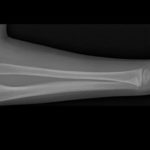

Unicameral(Simple) Bone Cyst

Courtesy: Prof Nabil Ebraheim,University of Toledo, Ohio, USA